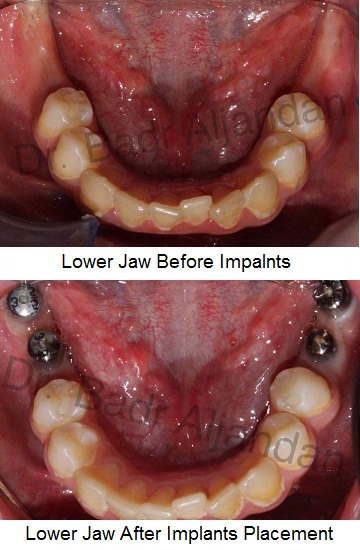

SURGICAL PROCEDURE

For most patients, the placement of dental implants involves two surgical procedures. First, implants are placed within your jawbone. For the first three to six months following surgery, the implants are beneath the surface of the gums gradually bonding with the jawbone. You should be able to wear temporary dentures and eat a soft diet during this time. At the same time, your dentist is forming new replacement teeth.

After the implant has bonded to the jawbone, the second phase begins. Dr. Al-jandan will uncover the implants and attach small posts that protrude through the gums and will act as anchors for the artificial teeth. When the artificial teeth are placed, these posts will not be seen. The entire procedure usually takes six to eight months. Most patients experience minimal disruption in their daily life.